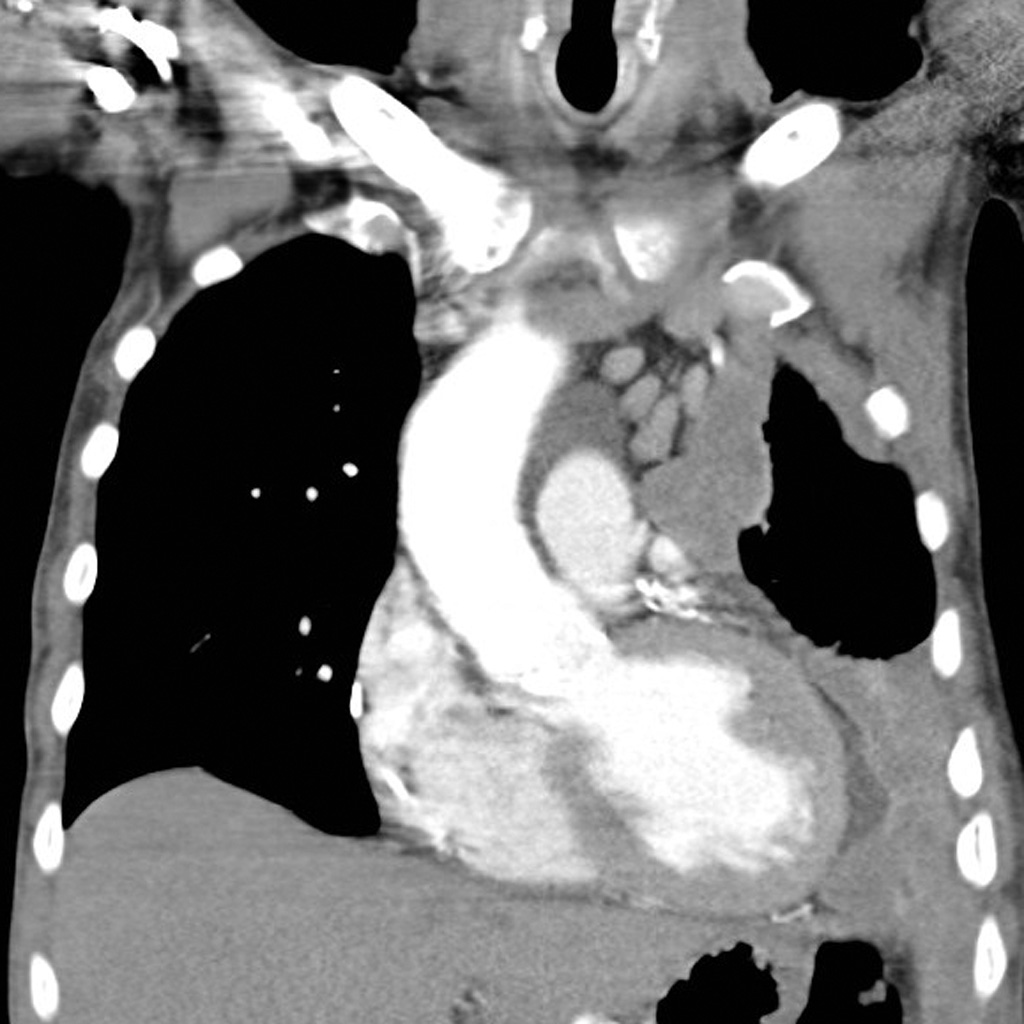

- Pleural malignant mesothelioma , Terjadi pada jaringan yang melapisi sekitar paru-paru dan merupakan jenis yang paling umum.

- Pericardial mesothelioma , terjadi pada jaringan yang melapisi disekitar jantung.